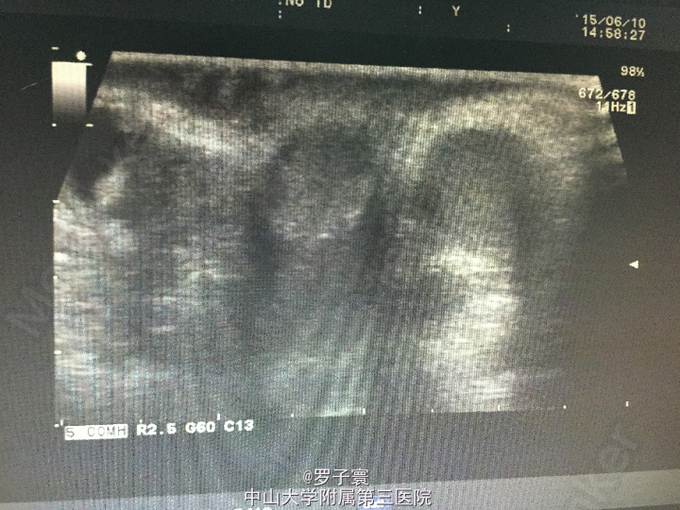

查体:阴茎呈男童外观,包茎,左侧阴囊空虚,未触及任何内容物,左侧腹股沟可触及睾丸样团块,质地软,大小1.4*0.6cm,无触痛,无粘连,站立活动后右侧阴囊可触及质软肿物,透过试验阳性,可扪及右侧睾丸,大小约1.5*0.8cm,触诊质地软,表面光滑,无硬结,无压痛,附睾、精索触诊不满意。生殖系彩超(我院,2015-06-10):双侧阴囊内睾丸缺如;双侧腹股沟部隐睾(左侧活动度大);右侧睾丸鞘膜积液。